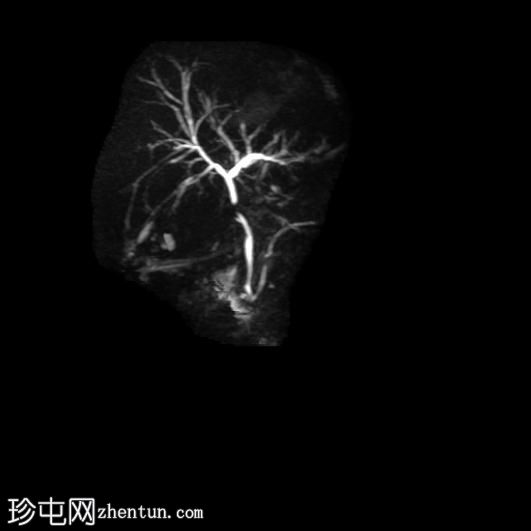

冠状位

MRCP

厚层扫描

胆囊切除术后,可见肝总管局部断裂,尤其是在胆囊管开口上方。该断裂伴有胆囊切除部位形成较大的血肿或胆汁瘤。

胆管损伤可能发生在手术过程中,导致胆汁渗漏到周围组织,从而形成血肿或胆汁瘤。这可能出现明显的临床症状,并可能需要进一步干预,具体取决于病情的严重程度和患者的临床表现。